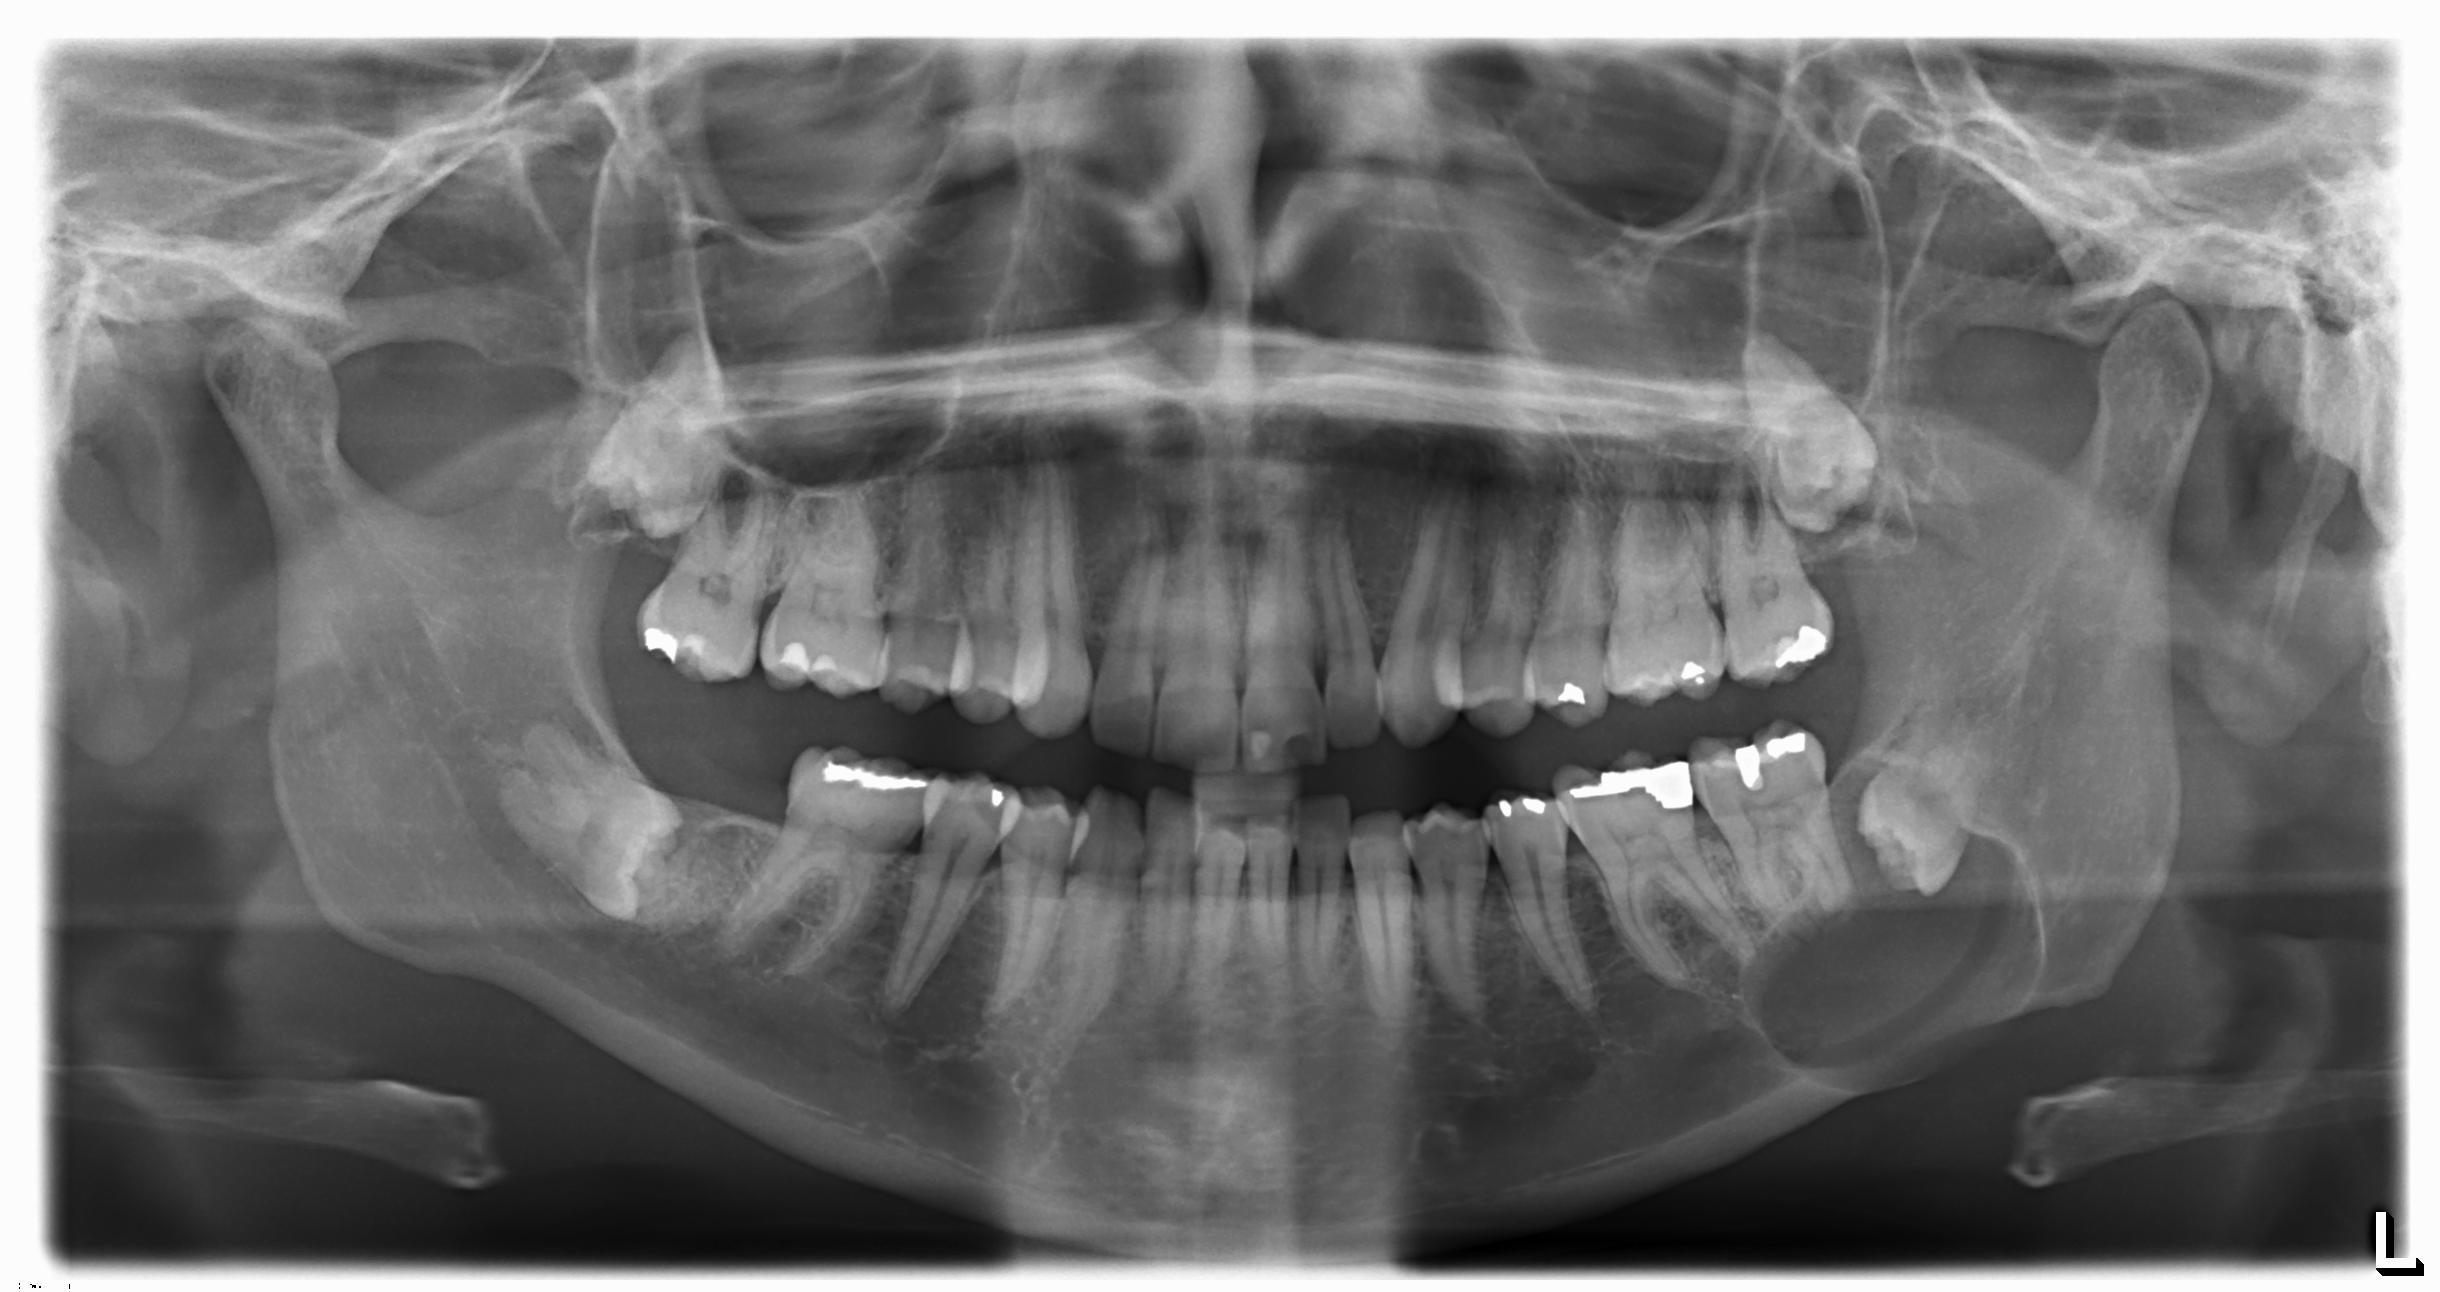

Wellthatsucks: Went to the dentist to fix a chipped tooth, spotted a cyst asserting its dominance over my jawbone